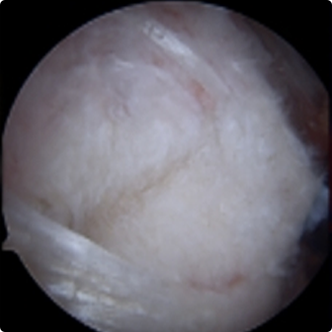

회전근개파열의 여러 모습들

회전근개파열의